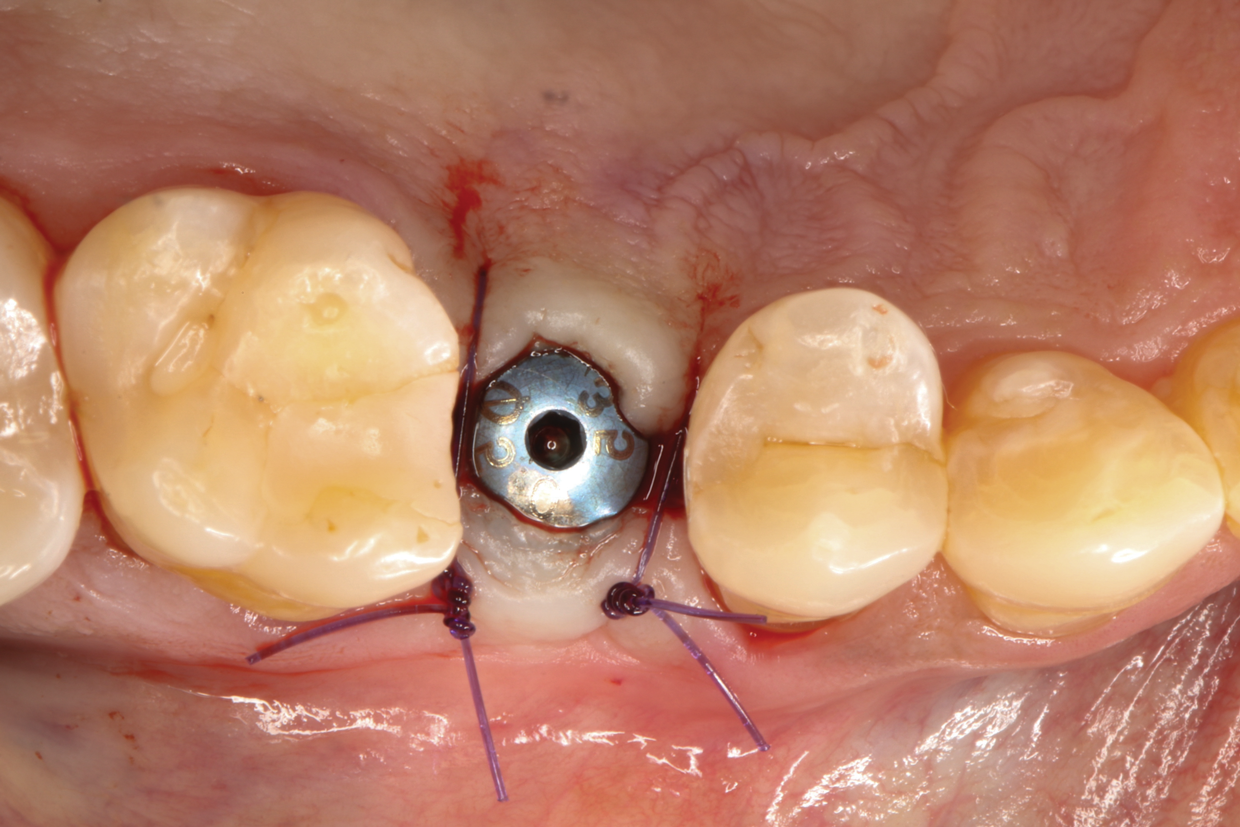

Fig 10. A healing cap was connected, and flaps were sutured with 4-0 absorbable sutures.

Figure 10

The patient returned 4 months later for implant placement with complete wound healing observed (Figure 7). Following local anesthesia via infiltration of 2% xylocaine with 1:100,000 epinephrine, a crestal incision was carried out over the edentulous area to allow for full-thickness flap elevation (Figure 8). Adequate alveolar bone dimensions for implant placement were observed (Figure 9). Optimal bone density and quality was confirmed during implant osteotomy preparation for placement of a 4.2 mm x 11 mm implant. Optimal insertion torque was recorded (45 Ncm). A healing cap was connected, and flaps were sutured with 4-0 absorbable sutures (Figure 10).